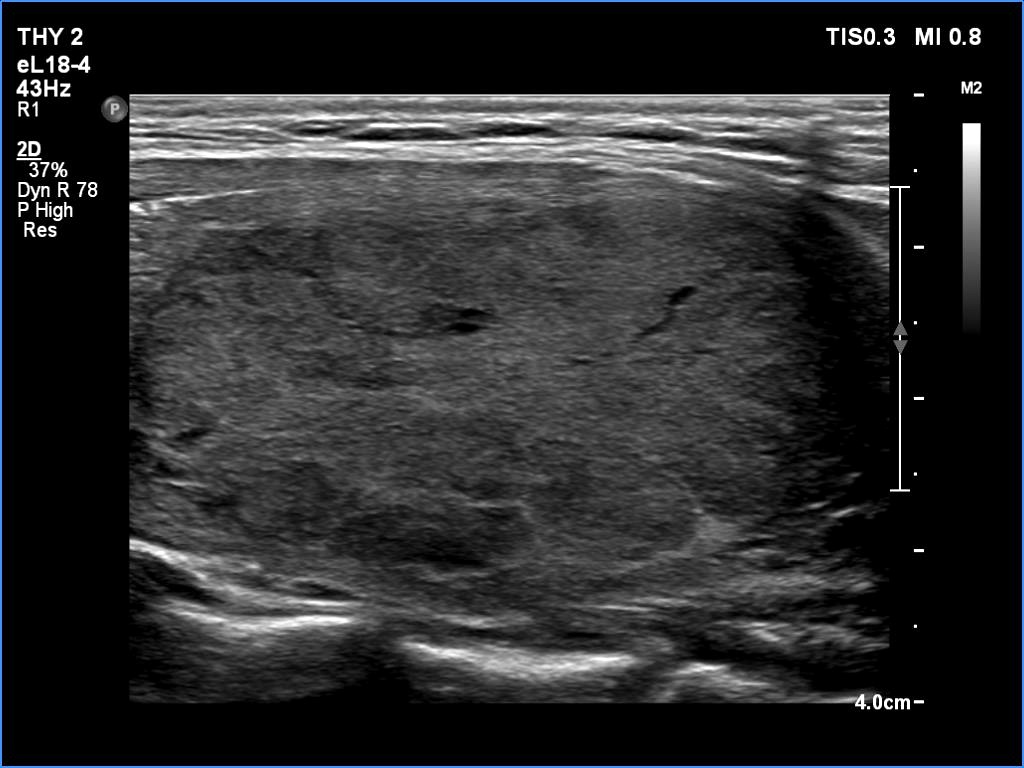

Comments. It is worth highlighting three changes. First, the nodule echogenicity has changed over time - from clearly hyperechoic to moderately hypoechoic. Secondly, the nodule substantially increased in size. This is the cause for the disappearance of the halo, due to the nodule growth, the capsule became invisible thin. Thirdly, the pattern of the intranodular hypoechoic parts has also changed.